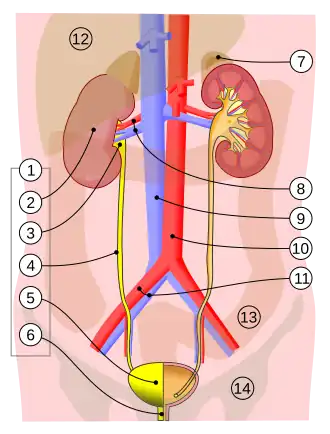

1. Human urinary system: 2. Kidney, 3. Renal pelvis, 4. Ureter, 5. Bladder, 6. Urethra. (Left side with frontal section) 7. Adrenal gland Vessels: 8. Renal artery and vein, 9. Inferior vena cava, 10. Abdominal aorta, 11. Common iliac artery and vein With transparency: 12. Liver, 13. Large intestine, 14. Pelvis | |